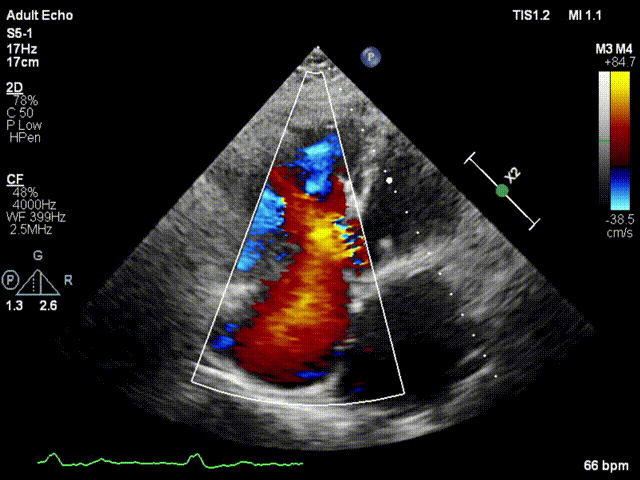

本次接受治療的患者是一名74歲的女性,14年前因風(fēng)濕性心臟病行二尖瓣生物瓣植入術(shù),合并房顫。近3年來反復(fù)因腹脹、納差、下肢水腫入院,藥物治療欠佳。心臟超聲顯示三尖瓣極重度反流(有效反流口面積:0.76cm²,反流容積:79ml),繼發(fā)性右房室增大及上、下腔靜脈增寬(右房上下徑*左右徑:52*41mm,右室左右徑:46mm,下腔靜脈:29mm),右室收縮功能正常,肺動(dòng)脈收縮壓 43mmHg,左心室射血分?jǐn)?shù)73% 。患者既往開胸手術(shù)史,術(shù)前評(píng)估STS 評(píng)分為7.02分,CRS 9分,無法接受體外循環(huán)下三尖瓣外科手術(shù)。面對(duì)這一傳統(tǒng)治療無法解決的困境,葛均波院士及其團(tuán)隊(duì)周達(dá)新教授、潘文志教授、張?jiān)床┦?、陳莎莎博士及心超室的潘翠珍教授、李偉教授?jīng)過討論決定,采用創(chuàng)新的Lux-Valve Plus系統(tǒng)為患者進(jìn)行經(jīng)血管三尖瓣置換。

手術(shù)在患者全麻狀態(tài)下進(jìn)行,采用經(jīng)右側(cè)頸靜脈作為入路,將裝載有人工瓣膜的輸送器緩慢推送至右心房;并在經(jīng)食道超聲和DSA的引導(dǎo)下小心調(diào)整輸送器角度,將輸送器送入右心室;逐步釋放瓣膜錨定裝置和盤片,調(diào)整瓣膜位置后,錨定瓣膜完成植入。術(shù)后右房壓明顯下降,從術(shù)前的25/10(16) mmHg降至術(shù)后即刻的12/7(10) mmHg,術(shù)后超聲提示人工三尖瓣同軸性良好,固定牢固,無反流及瓣周漏,手術(shù)室即刻拔除氣管插管。